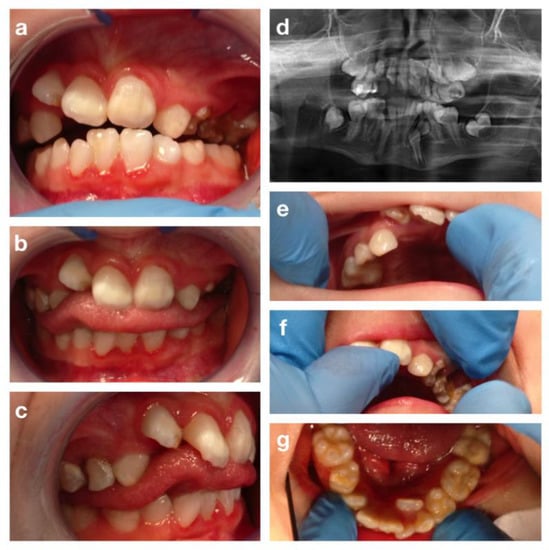

3.4. The Cornelia De Lange Syndrome

3.5. Progeroid Syndromes